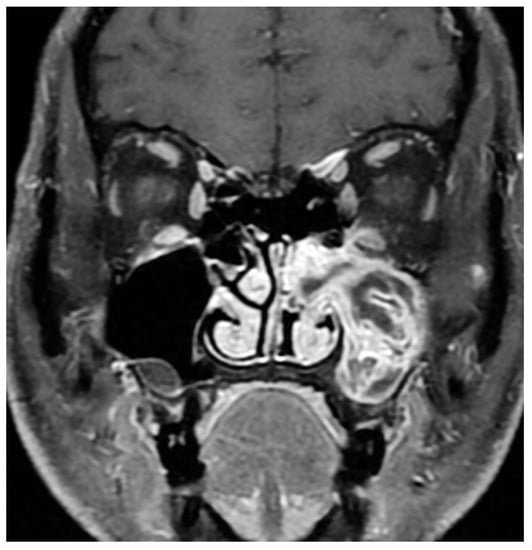

3. Imaging

- Jeon, T.Y.; Kim, H.J.; Chung, S.K.; Dhong, H.J.; Kim, H.Y.; Yim, Y.J.; Kim, S.T.; Jeon, P.; Kim, K.H. Sinonasal inverted papilloma: Value of convoluted cerebriform pattern on MR imaging. AJNR Am. J. Neuroradiol. 2008, 29, 1556–1560. [Google Scholar] [CrossRef] [PubMed]

- Oikawa, K.; Furuta, Y.; Oridate, N.; Nagahashi, T.; Homma, A.; Ryu, T.; Fukuda, S. Preoperative staging of sinonasal inverted papilloma by magnetic resonance imaging. Laryngoscope 2003, 113, 1983–1987. [Google Scholar] [CrossRef]

- Kasbekar, A.V.; Swords, C.; Attlmayr, B.; Kulkarni, T.; Swift, A.C. Sinonasal papilloma: What influences the decision to request a magnetic resonance imaging scan? J. Laryngol. Otol. 2018, 132, 584–590. [Google Scholar] [CrossRef] [PubMed]

- Zhang, L.; Fang, G.; Yu, W.; Yang, B.; Wang, C.; Zhang, L. Prediction of malignant sinonasal inverted papilloma transformation by preoperative computed tomography and magnetic resonance imaging. Rhinology 2020, 58, 248–256. [Google Scholar] [CrossRef]